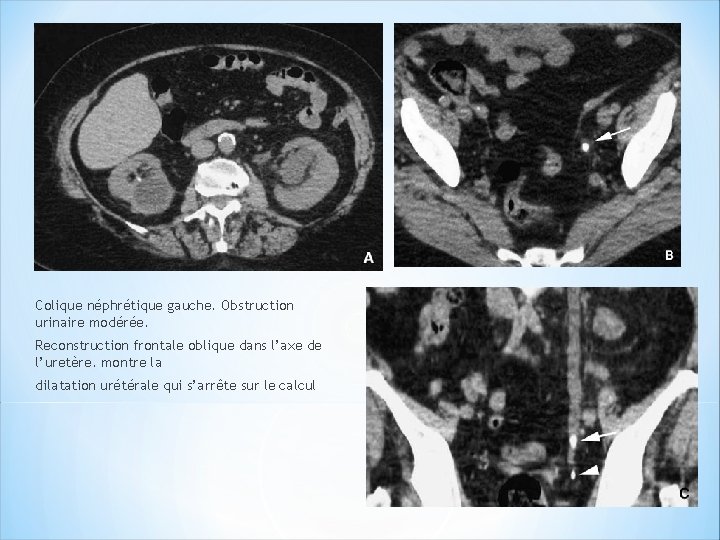

Dilatation modérée des cavités gauches +rem aniements inflammatoires de la graisse. Retard d’opacification du parenchyme Reconstruction 2 D frontale oblique. Arrêt de la dilatation au niveau du calcul avec oedème de la graisse périurétérale.

Colique néphrétique gauche. Obstruction urinaire modérée. Reconstruction frontale oblique dans l’axe de l’uretère. montre la dilatation urétérale qui s’arrête sur le calcul